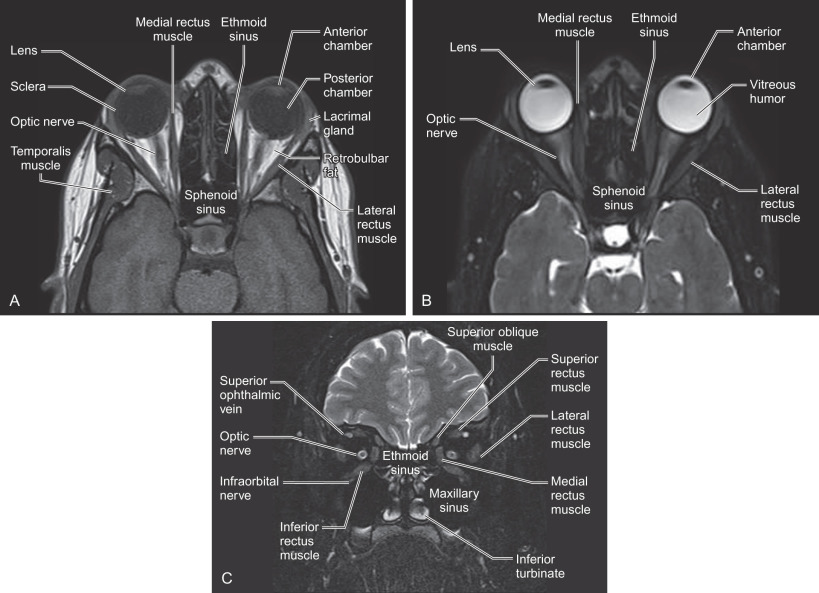

Advantages of MRI include noninvasive imaging without ionizing radiation, and soft tissue resolution in multiple planes that is superior to computed tomography ( Figs. 1.2.9 and 1.2.10 ). In the setting of craniomaxillofacial trauma, MRI can be used to evaluate the optic nerve for traumatic optic neuropathy (TON) ( Fig. 1.2.11 ), as well as herniation of orbital contents into the adjacent maxillary sinus or traumatic encephaloceles. A study by Freund et al. demonstrated that MRI showed the inferior rectus muscle to be herniated through the orbital floor fractures twice as often as when compared to the evaluation of the orbital contents using CT. Although MRI is suboptimal in assessing cortical bone given the paucity of hydrogen atoms, it can depict bone marrow edema associated with chronic complications of trauma such as mandibular osteomyelitis, ischemic necrosis of the condylar head, and traumatic damage to the articular disc. The disadvantages of MRI include high cost, long scan times, metallic hardware that can obscure adjacent structures, and other relative contraindications to MRI.